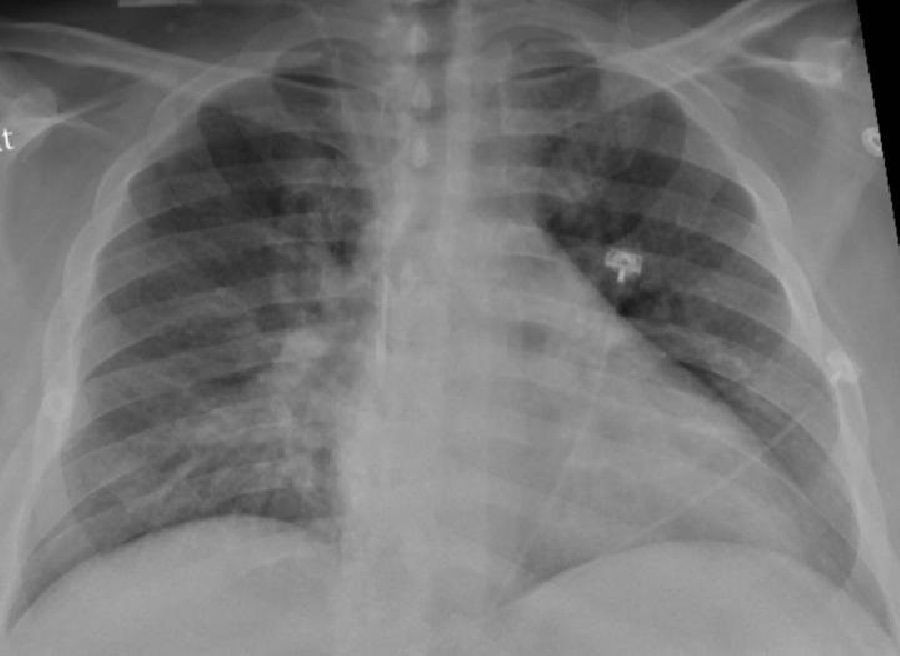

Un nuevo atlas celular de los pulmones revela por qué el virus es mortal y diferente

Un nuevo estudio del Colegio de Médicos y Cirujanos Vagelos de la Universidad de Columbia y del Centro Oncológico Integral Herbert Irving (Estados Unidos) ha dibujado la imagen más detallada hasta ahora de la infección por SARS-CoV-2 en el pulmón, revelando los mecanismos que dan lugar a la COVID-19 letal, y puede explicar las complicaciones a largo plazo y mostrar cómo la COVID-19 difiere de otras enfermedades infecciosas.

Aunque el estudio analizó los pulmones de pacientes que habían fallecido a causa de la enfermedad, proporciona pistas sólidas sobre los motivos por los que los supervivientes de la COVID-19 grave pueden experimentar complicaciones respiratorias a largo plazo debido a la cicatrización pulmonar.

Este nuevo estudio es único con respecto a otras investigaciones, ya que examina directamente el tejido pulmonar (en lugar de esputo o lavados bronquiales) utilizando perfiles moleculares unicelulares que pueden identificar cada célula en una muestra de tejido y registrar la actividad de cada célula, lo que da lugar a un atlas de células en el pulmón tras la COVID-19.

El equipo examinó los pulmones de 19 individuos que murieron de COVID-19 y se sometieron a una autopsia rápida (a las pocas horas de la muerte), durante la cual se recogieron tejidos pulmonares y de otro tipo y se congelaron inmediatamente, y los pulmones de pacientes que no tenían COVID-19. En colaboración con investigadores de la Universidad de Cornell, los investigadores también compararon sus resultados con los pulmones de pacientes con otras enfermedades respiratorias.

En comparación con los pulmones normales, los pulmones de los pacientes con COVID-19 estaban llenos de células inmunitarias llamadas macrófagos, según el estudio. Normalmente, durante una infección, estas células mastican los patógenos pero también regulan la intensidad de la inflamación, lo que también ayuda en la lucha.

"En COVID-19, observamos la expansión y la activación incontrolada de los macrófagos, incluidos los macrófagos alveolares y los macrófagos derivados de los monocitos. Están completamente desequilibrados y permiten que la inflamación aumente sin control. Esto da lugar a un círculo vicioso en el que entran más células inmunitarias que causan aún más inflamación, lo que en última instancia daña el tejido pulmonar", destaca Izar.